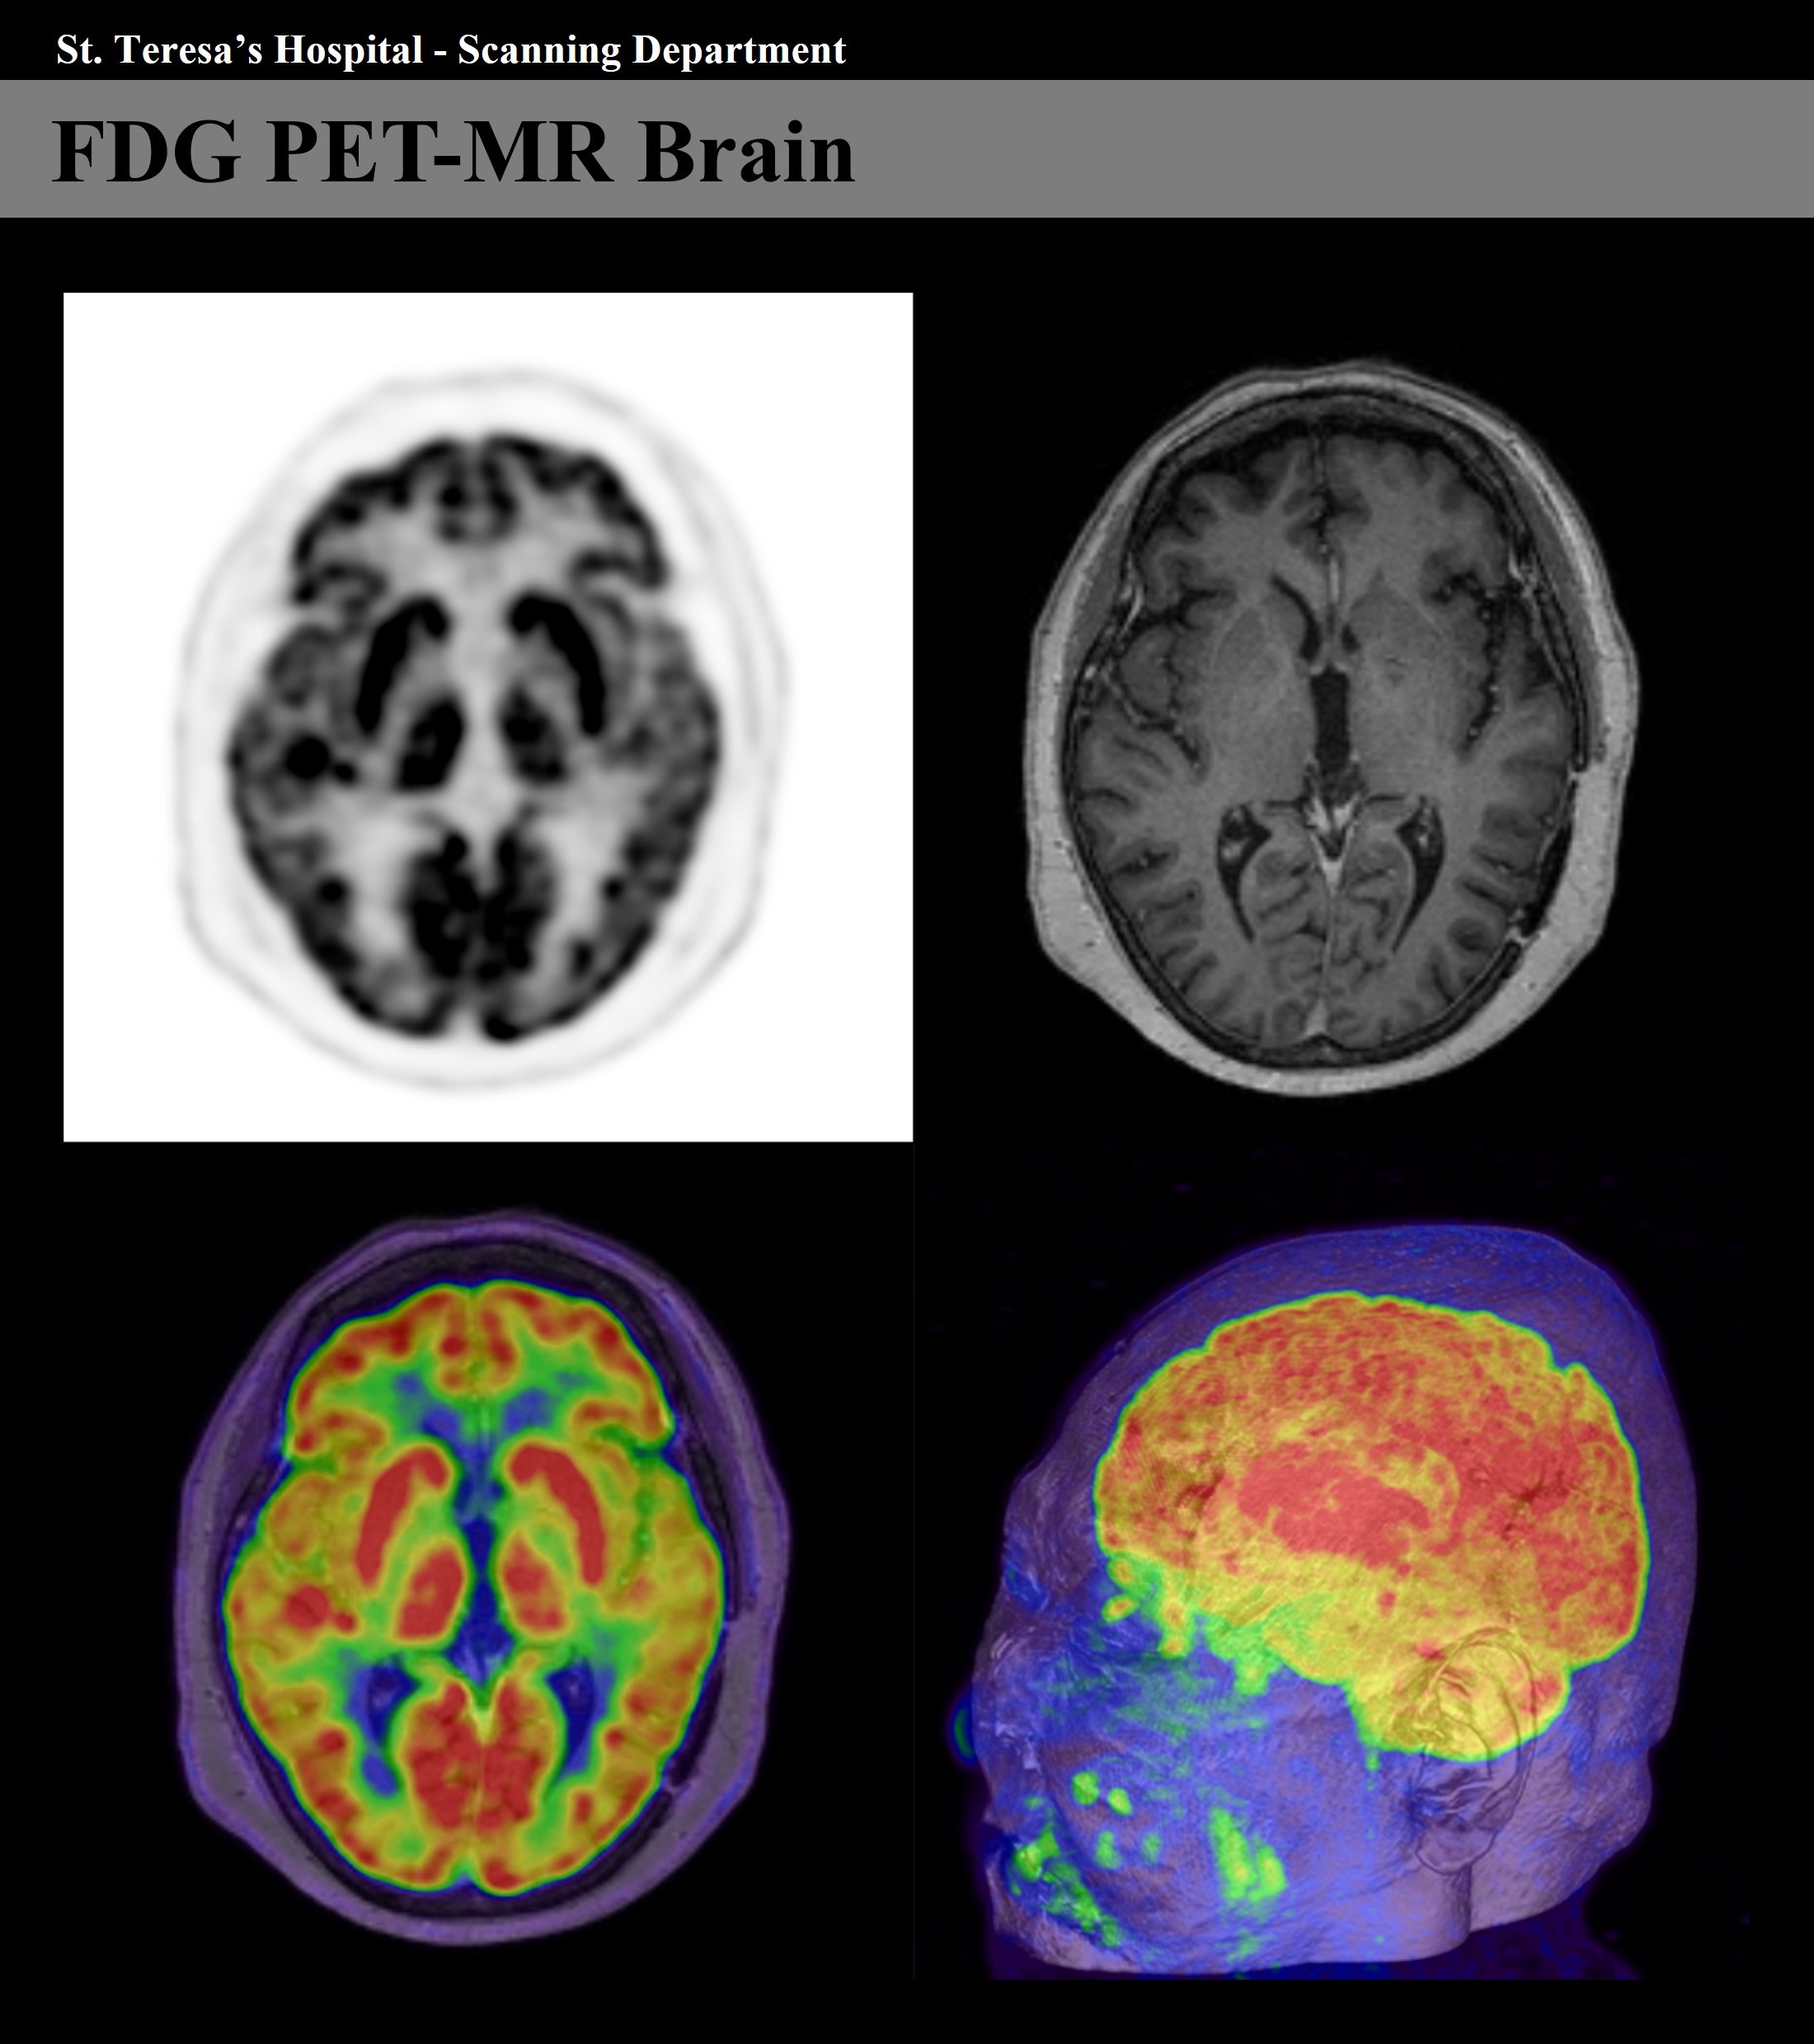

正電子磁力共振掃描 (PET-MR)

什麼是正電子磁力共振掃描 (PET-MR)?

正電子磁力共振掃描是揉合了正電子掃描和磁力共振掃描兩種技術於單一系統中,利用嶄新同位素影像技術來顯示疾病細胞在軟組織中的擴散跡像。

正電子磁力共振掃描如何幫助病人?

- 提供高解像度的軟組織影像,有助辨識腫瘤疾病。

- 比正電子電腦掃描減少至少百分之五十的輻射劑量。

- 同時進行正電子及磁力共振兩種掃描。

- 有助對阿茲海默症及其他腦退化症等作出有效評估。